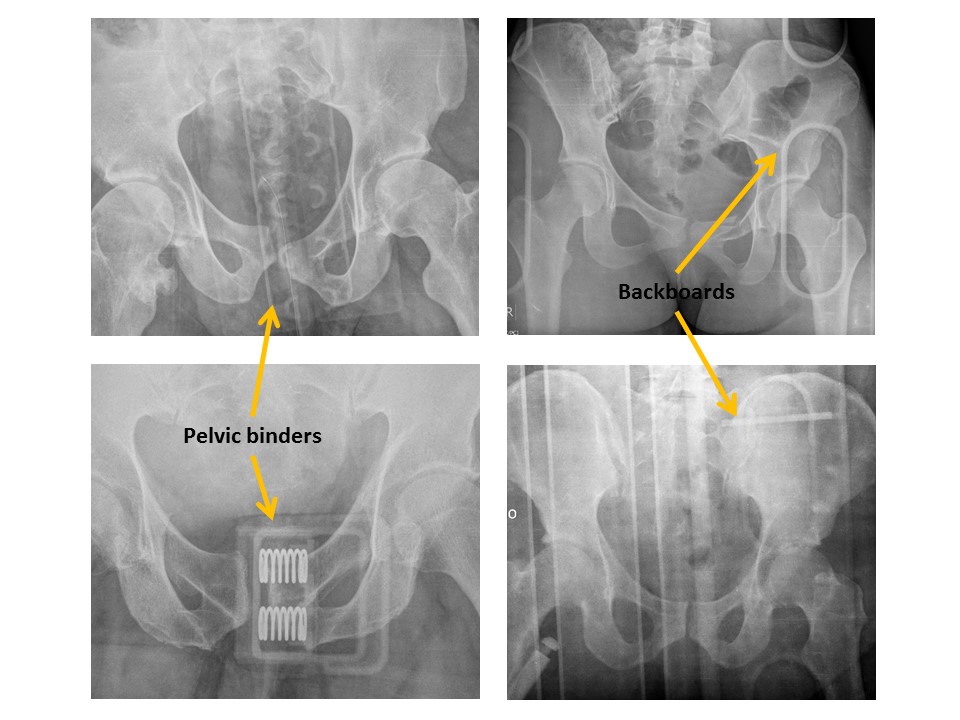

IMAGE QUALITY

Portions of the patient’s anatomy are excluded from the field of view [Yes/No]

There are external structures overlying the patient’s pelvis, such as a backboard. [Yes/No]

The image is rotated. [Yes/No]